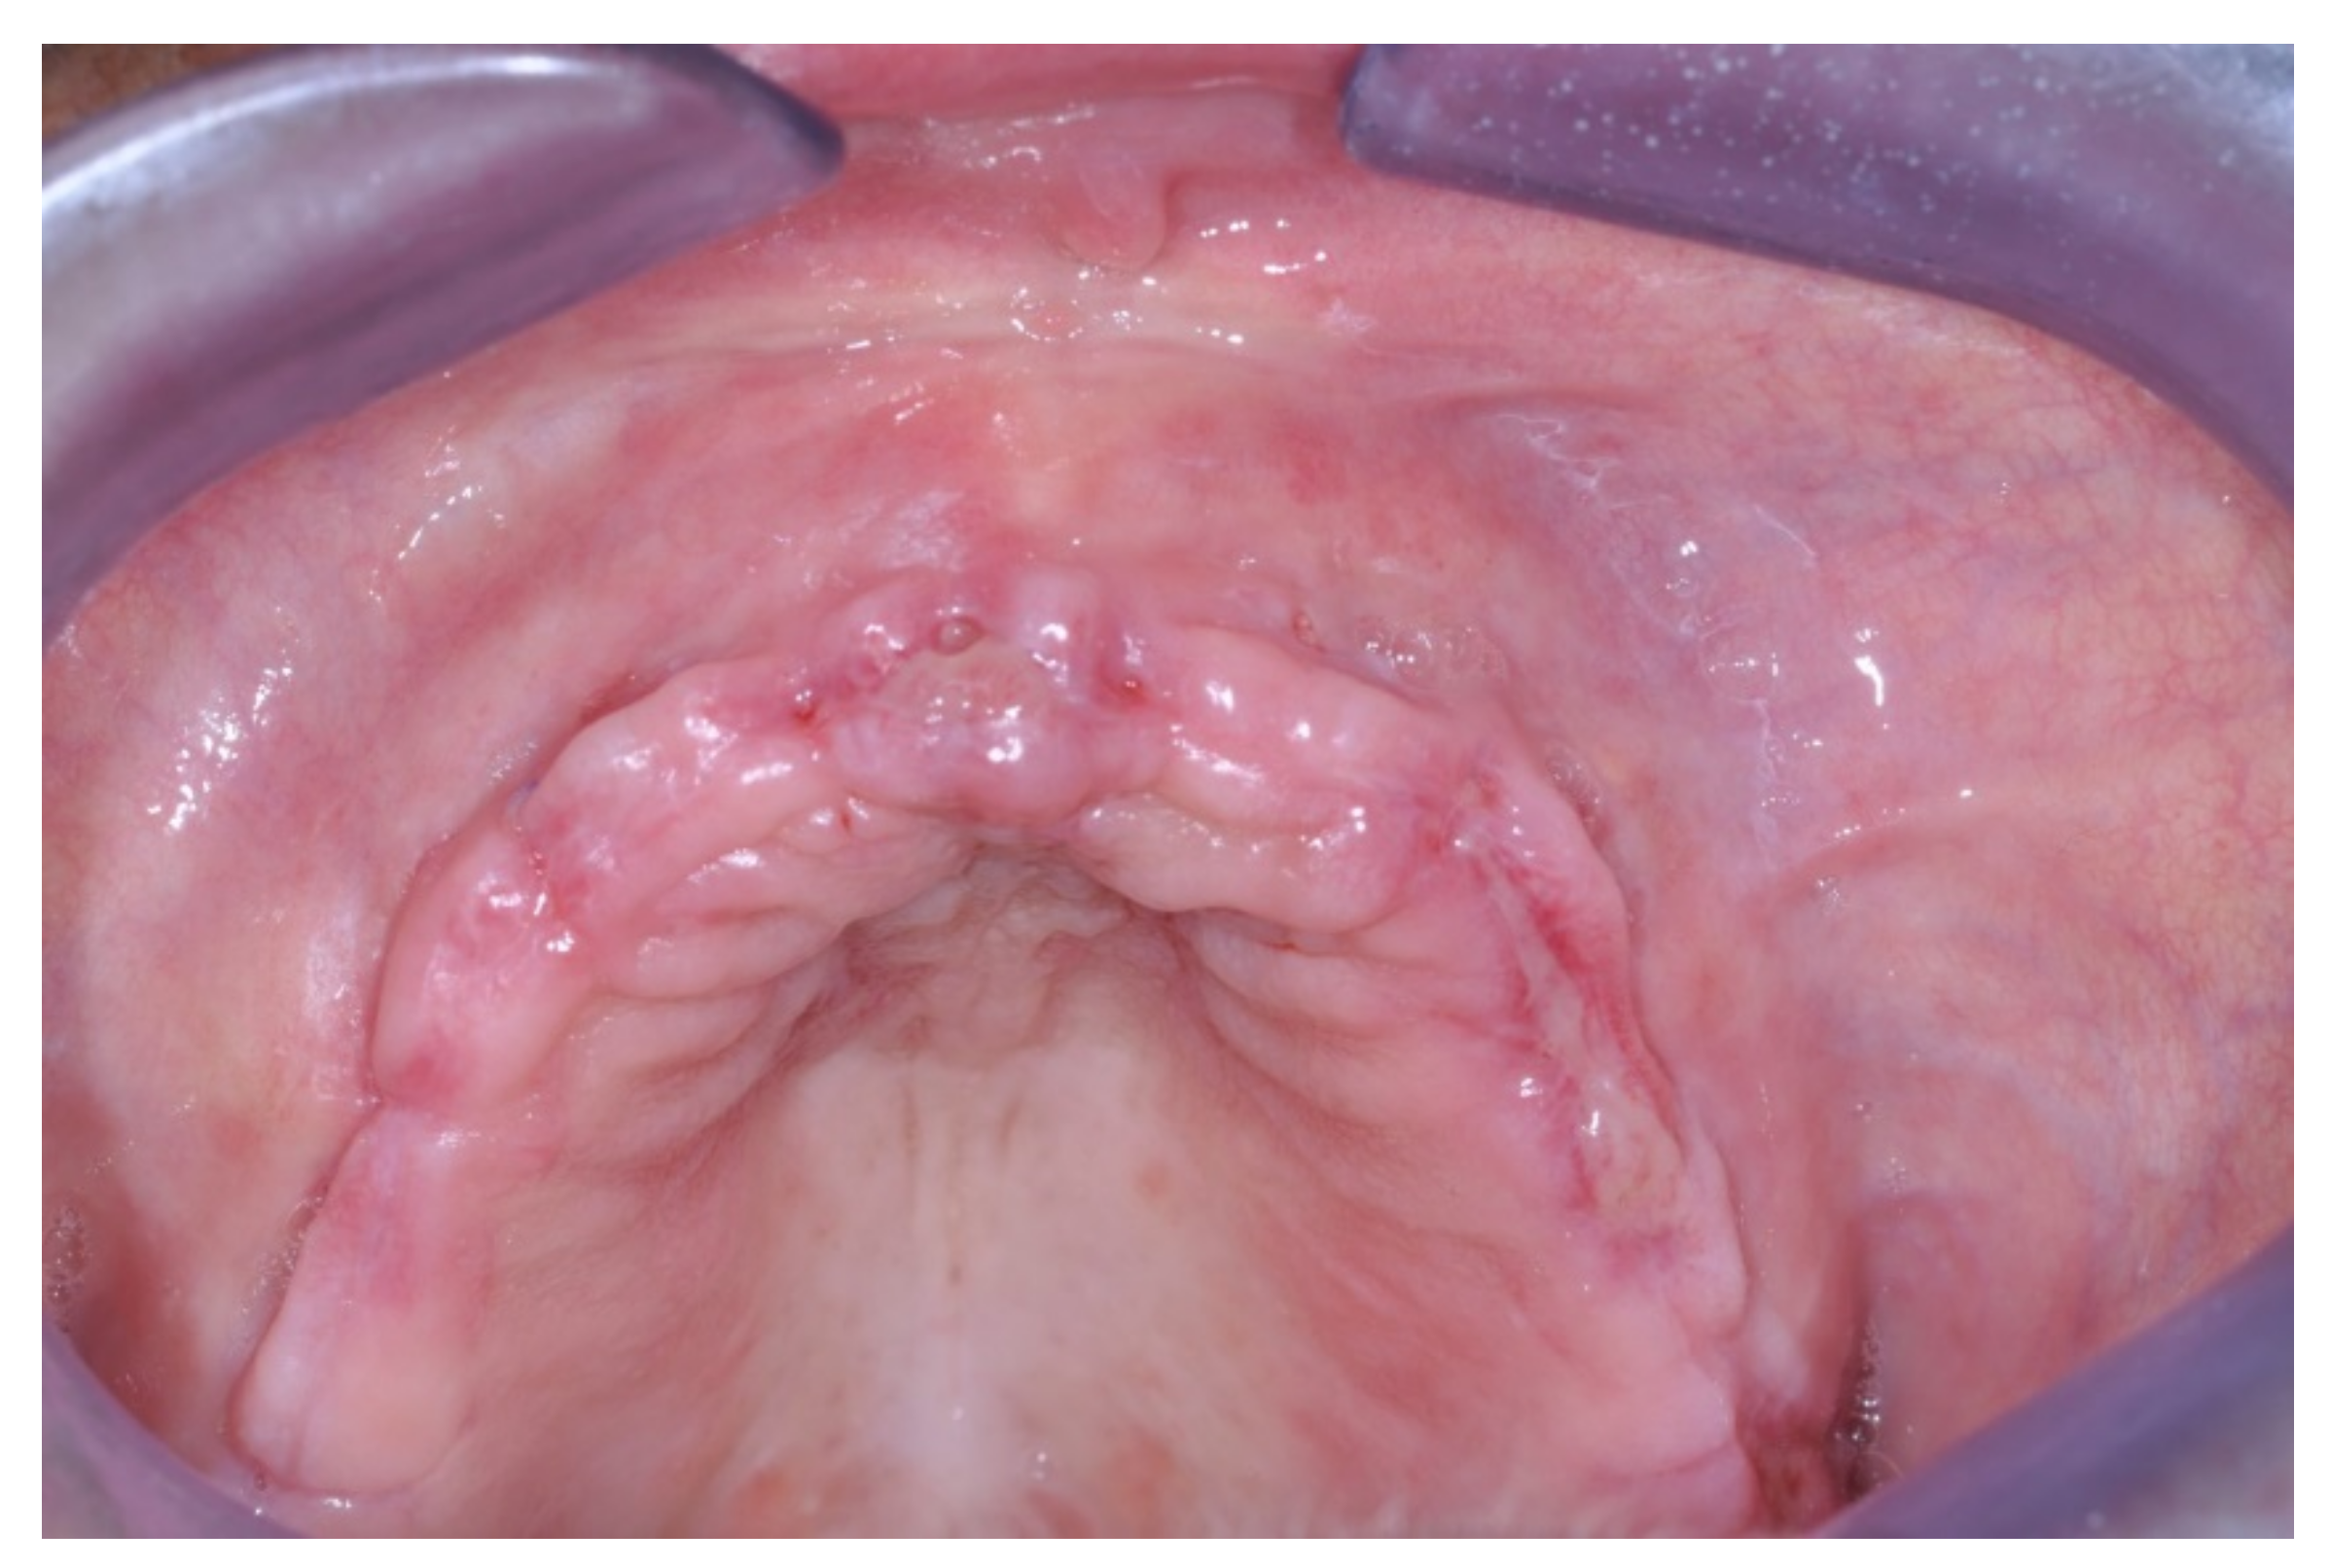

Patients rinsed with a chlorhexidine mouthwash (0.2%) for 1 min immediately prior to the intervention. Local anesthesia were administered using mepivacaine with adrenaline at ratios of 1:100,000 or 1:50,000. Crestal incisions were made with releasing incisions far away from the future membrane positioning and full thickness flaps were elevated. After the meticulous removal of all residual soft tissues in the regenerating site, copious bleeding was induced using a bone scraper (Safescraper Curve TWIST, META, Reggio Emilia, Italy) (Figure 1). A prosthetically guided implant placement was performed following the instructions of manufacturer (Thommen Medical, Grenchen, Switzerland). Only 1 patient had implants placed 9 months after bone augmentation because the initial bone thickness did not permit the primary stabilization of the implant fixtures (Figure 2, Figure 3, Figure 4, Figure 5, Figure 6, Figure 7 and Figure 8).

Figure 2. Sequence of treatment phase of the only patient who was treated according a 2-stage approach: stage 1 GBR procedure and stage 2 implant placement (pre-operative view).

Figure 3. Intra-surgical view prior to horizontal GBR.

In 9 out of 10 patients, the implants were inserted at the same time as regeneration and loaded 8–9 months later. Only in 1 patient were the implants placed 9 months after the augmentation procedure.